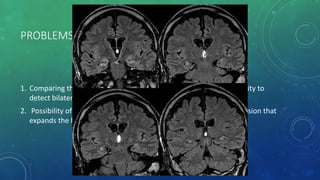

PROBLEMS IN DIAGNOSINS MTS WITH MRI

1. Comparing the volumes of the two hippocampi, including the inability to

detect bilateral hippocampal sclerosis .

2. Possibility of false lateralization in patients with an epileptogenic lesion that

expands the hippocampus.